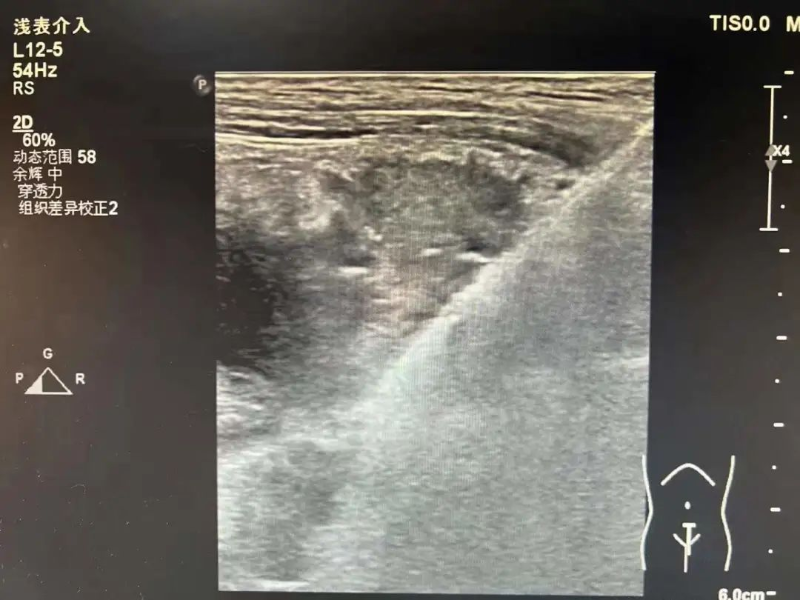

为进一步诊断病情,3月17日在陈勇辉超声引导下,超声医学科蒋朝霞主任医师为林伯伯进行肺肿瘤穿刺活检。超声引导下以右肺肿瘤最清楚处为目标,用穿刺针沿着引导线刺入,通过针尖穿越肿瘤触发活检枪进行活检。穿刺后,林伯伯无不适。我院超声医学科成功完成穿刺活检,为患者进行专科治疗做“最强辅助”,充分体现了我院超声医学科能力水平的综合提升,让患者能就近就医、就近诊断,为患者减轻看病就医经济负担和解决奔波劳碌的问题。